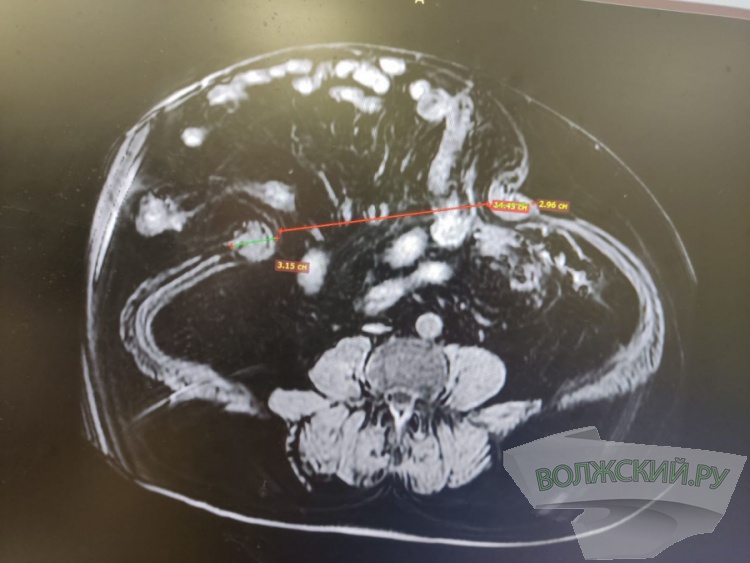

Как рассказали Волжский.ру в комитете здравоохранения, пациенту больше 65 лет, а грыжу ему диагностировали два года назад. За это время она сильно увеличилась в размерах. Также он страдает сахарным диабетом, а в 2021 году пережил циркулярный инфаркт миокарда. При этом мужчина продолжает работать и ведёт активный образ жизни. Со слов пациента и его родных, по месту жительства отказались оперировать из-за высокого риска и размеров грыжи. Помочь мужчине со сложной патологией взялись медики из Волжского. Врач-хирург Иван Шестопалов провел с пациентом несколько дистанционных консультаций, собрал данные, назначил необходимые исследования, провёл консультации с анестезиологами-реаниматологами. Во время предоперационного обследования у него выявили желчекаменную болезнь, которая протекала бессимптомно. Бригада врачей решила провести больному симультанную операцию с использованием принципов мультииодальной анальгезии, во время которой одновременно проводится до пяти различных хирургических манипуляций.

В Волжский воронежец прибыл за два дня до операции. Мужчине за один «приём» сделали грыжесечение, холецистэктомию и заднюю сепарационную пластику передней брюшной стенки с использованием сетчатого импланта. Благодаря этому удалось уменьшить нагрузку на организм и сократить сроки лечения и восстановления. Пациента на 6 сутки выписали в удовлетворительном состоянии.